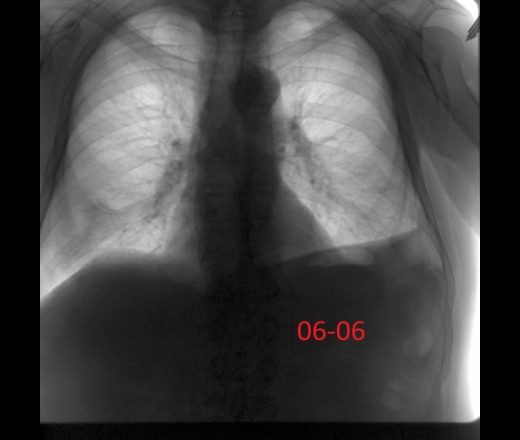

Мужчина 60лет. Диагностическая флюорография, 22 мая был поставлен диагноз пневмония с\д справа, пришел к нам на контроль второй раз.  Думаю все хорошо можно отпускать? Ваше мнение коллеги?

Да, динамика положительная, 4 сегмент с гиповентиляцией. Ограничился бы рентген контролем ч\з 1-1.5 мес.

Слева над диафрагмой дисковидный ателектаз?

Да нет, купол диафрагмы. (с учетом 22.05, 06.06.)

По всей видимости плеврит перенесен...

Динамика положительная. Слева облитерация костодиафрагмального синуса вследствии перенесенного плеврита